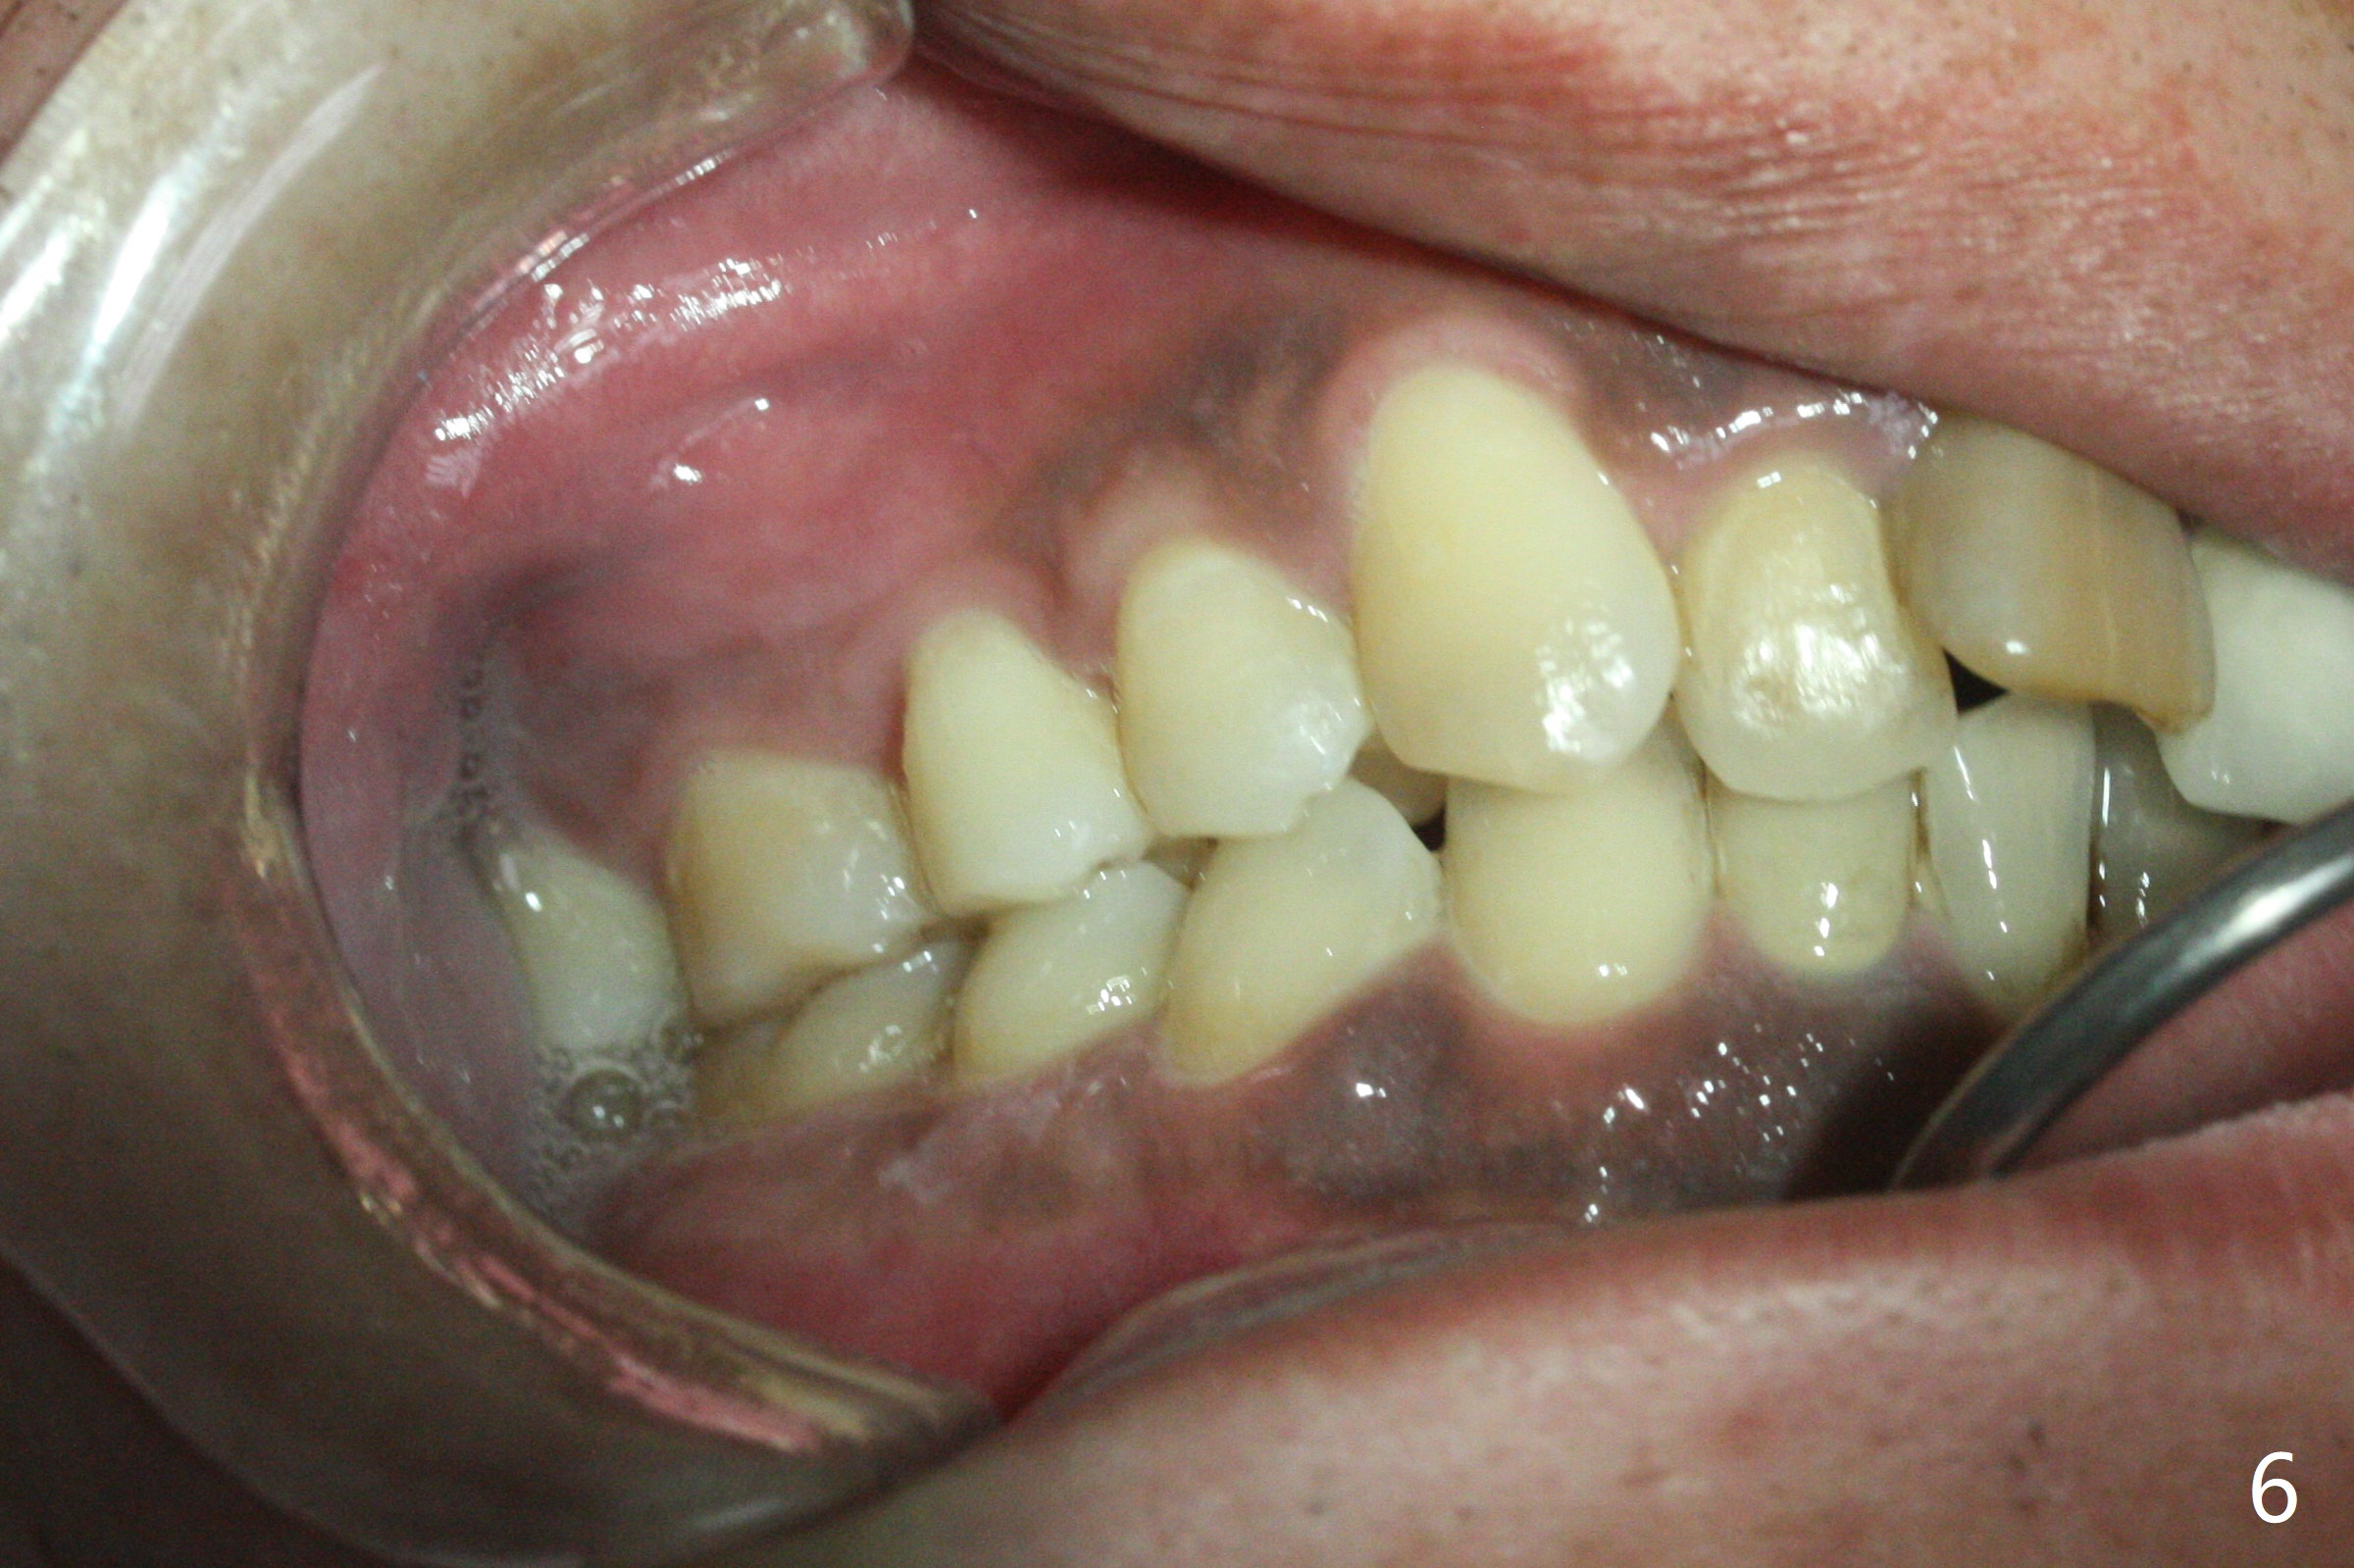

Class II半个牙。这个不用拔牙,Molar distalizaton 和expansion 就可以解决。Oral scan and submit it to Unismile. 建模后。我来帮您设计。张。两个中切牙,位置可以不用排得太完美。排到半程的位置,然后用重做的牙冠来调齐。这样,能减少一些复发的势能。Harry Hu